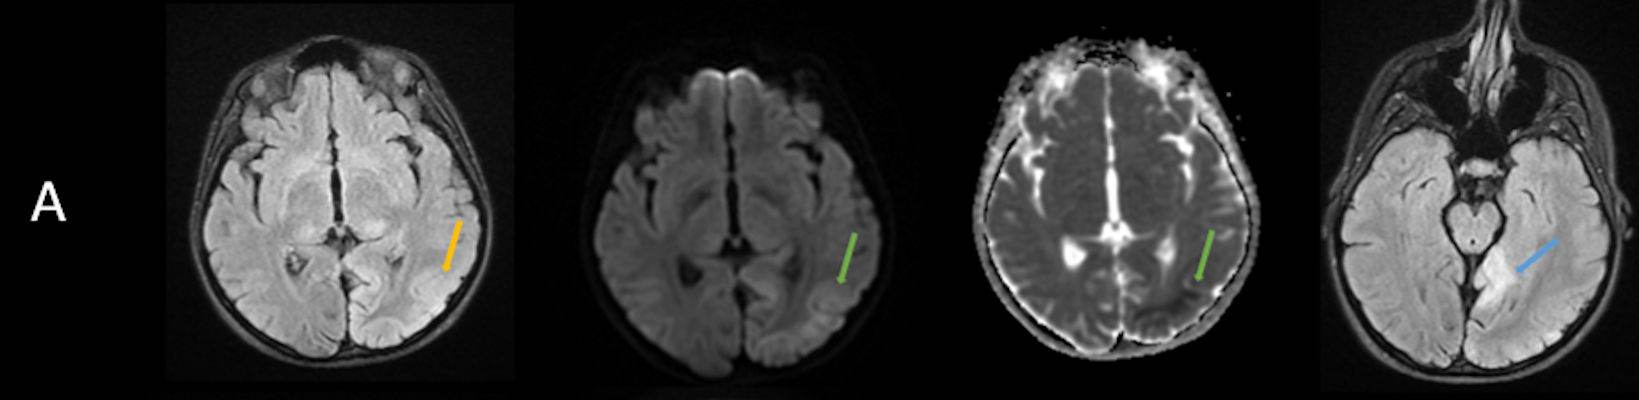

- A) Aksiyel FLAIR görüntülerde parietooksipital lobda kortikal hiperintensite (ok) ve difüzyon görüntülerde kısıtlanma alanları izleniyor (oklar). Ertesi gün çekilen kontrol MRG’de FLAIR serilerde yeni gelişen oksipital bölgede kortikal hiperintensite (ok) izlenmektedir.

- MELAS sendromunun radyolojik özellikleri, klasik iskemik inmeden farklı olarak vasküler sulama alanlarına uymayan ve migratuar stroke-benzeri lezyonlar ile karakterizedir.

- MRG’de akut fazda T2/FLAIR hiperintensiteyle birlikte giral şişme ile karakterize enfarkt-benzeri lezyonlar ve subkortikal beyaz cevher tutulumu görülür. DWI’da artmış sinyal dikkat çekmekle birlikte ADC değerlerinin normal ya da hafif artmış olması, baskın sürecin vazojenik ödem olduğunu gösterir.